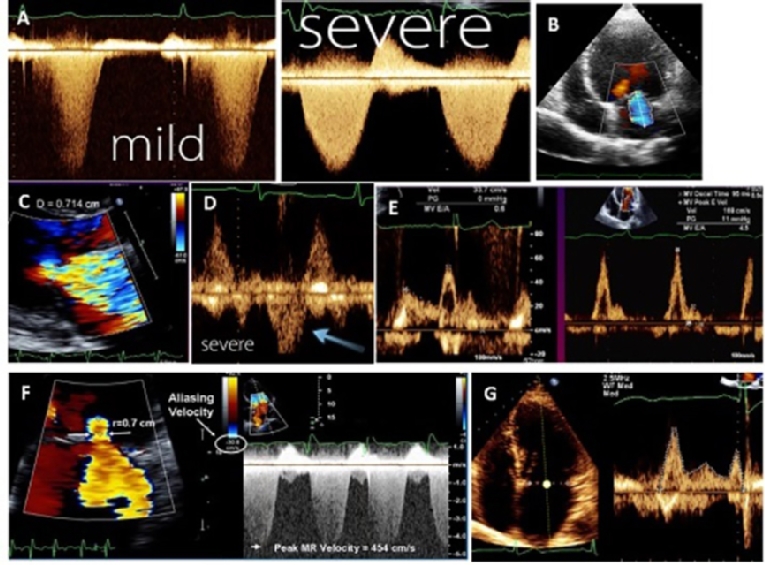

Using continuous wave Doppler, if the signal is similar in density to that of antegrade flow, this suggests significant MR, whereas a faint signal or an incomplete envelope is typical of mild MR (Figure 1A).

A colour Doppler imaging MR jet indicates the presence of MR. Appropriate adjustment of the gain setting is important to avoid underestimation and overestimation of MR severity. It can help in understanding the mechanism of MR through the direction of the MR jet. For example, in MR secondary to leaflet tethering, the regurgitant jet points towards the restricted leaflet, while in MV prolapse the regurgitant jet points away from the prolapsed leaflet. Measurement of the MR jet area alone or indexed by left atrium area is not valid for the severity because the jet area is very dependent on the mechanism of MR and usually underestimates the severity with the eccentric jet. In case of a normal MV structure, normal LV and LA size, a small central jet area of <4.0cm2 (or <10% of LA area) in multiple views is usually mild MR (Figure 1B).

The VC is defined as the smallest, highest-velocity region of a flow jet and is typically located at or just below the regurgitant orifice. Its width should be measured in a long-axis imaging plane perpendicular to the mitral leaflet closure. The VC is independent of flow rate and driving pressure. It can be used for central and eccentric jets and is accurate in acute MR. However, it is not valid for multiple jets. A VC width <0.3 cm denotes mild MR and a VC width >0.7 cm is specific for severe MR. Intermediate values of VC width (0.3-0.7 cm) do not mean that MR is moderate; confirmation by other quantitative methods is needed (Figure 1C).

Reduced systolic velocity in >1 pulmonary vein and even reverse flow indicates severe MR. However, increased left atrial pressure of any cause can result in blunted pulmonary venous systolic flow (Figure 1D). Absence of flow reversal should not be used for exclusion of significant MR. It can be false negative if the jet is directed away from pulmonary veins, e.g., highly eccentric MR and/or severely dilated left atrium. On the other hand, if the MR jet is small but eccentric and directed towards the pulmonary vein, blunted or reverse flow can be recorded in this pulmonary vein (false positive).

Using pulsed Doppler at the tip of the MV, early filling (E-wave) usually dominant (E velocity >1.5 m/s) indicates severe MR due to increased forward flow across the MV. If the A-wave is dominant, severe MR can be excluded (Figure 1E).

Effective regurgitant orifice area (Figure 1F).

The flow acceleration proximal to the regurgitant orifice results in a concentric proximal isovelocity surface area (PISA). PISA is based on the fact that, near the regurgitant orifice, the blood is disposed in hemispheric layers, having the same velocity at a certain distance from the orifice. Lowering the velocity at which aliasing appears to 15-40 cm/s, all the “layers” with a higher velocity will have the aliasing phenomenon. Measuring the first aliasing hemisphere is a marker of regurgitation degree [3]. PISA measurement requires a narrow sector of colour with zoom mode and a shift of the Nyquist limit to be between 15-40 cm/sec. Four formulas are used for calculation:

• PISA = 2πr2 (assuming that PISA is a hemisphere).

• Regurgitant flow rate (RFR) = PISA x aliasing velocity (which is equal to the Nyquist limit on the colour scale).

• Regurgitant orifice area (ROA) = RFR/max MR velocity. Effective ROA (EROA) <0.20 cm2 indicates mild MR and ≥0.40 indicates severe MR.

• Regurgitant volume (RV) = ROA x velocity time integral (VTI) of MR. RV <30 ml/beat indicates mild MR while ≥60 ml/beat indicates severe MR.

Volumetric measurement

Quantification of RV and regurgitant fraction (RF) is based on calculation of stroke volume (SV) across the MV and across another non-regurgitant valve (aortic or pulmonic). The formula used for SV calculation is: SV=cross-section area x VTI (Figure 1G). Subtraction of the SV obtained at two sites is used to calculates RV. RF is calculated as a percentage of RV to SV across the MV. RF <30% indicates mild MR while ≥50% indicates severe MR. ROA can also be obtained by the formula: ROA= RV/VTI of MR. To calculate SV across the aortic valve, a parasternal long-axis view is used to measure LV outflow tract (LVOT) diameter at the level of the aortic valve annulus, just proximal to the cusps, and an apical 5-chamber view to measure the VTI of the LVOT using pulsed wave Doppler placing the sample volume at the level of the same point where the LVOT diameter was measured. To calculate SV across the MV, an apical 4-chamber view is used to measure the MV annulus diameter and to measure the VTI of the MV using pulsed wave Doppler placing the sample volume at the tip of the leaflet.

Figure 1. Methods used for MR quantification. Continuous Doppler tracing showing dense signal with severe MR and faint with mild MR (A), tracing of MR jet area (B), width of vena contracta (C), reversal of pulmonary venous flow (D), dominant E-wave of mitral inflow in severe MR (E), calculation of MR using PISA method (F), and volumetric measurement of stroke volume across the MV (G).